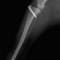

■ 症例22 ポメラニアン 1歳5か月 去勢雄

左後肢の挙上を主訴に来院した。整形学的検査、レントゲン検査より左右の膝蓋骨脱臼(左GradeⅡ〜Ⅲ、右Grade Ⅱ)を認めた。また、脛骨の前方引き出し試験の際に、引き出し兆候は認められないものの、疼痛が認められたため、前十字靭帯の損傷が疑われた。術中における、目視および関節内の操作によって、前十字靭帯の損傷や過伸展といった異常が認められなかったため、膝蓋骨脱臼の整復のみ実施した。手術手技は縫工筋及び内側広筋の解放、脛骨粗面の外側転位、滑車ブロック形造溝術、内外側関節包の縫縮を実施した。本症例は跛行もなく経過良好である。しかし、頸骨高平部の角度(TPA)が 右26.2°、左24.9°であり、解剖学的に前十字靭帯損傷のリスクが高いことから今後の経過に注意が必要である。